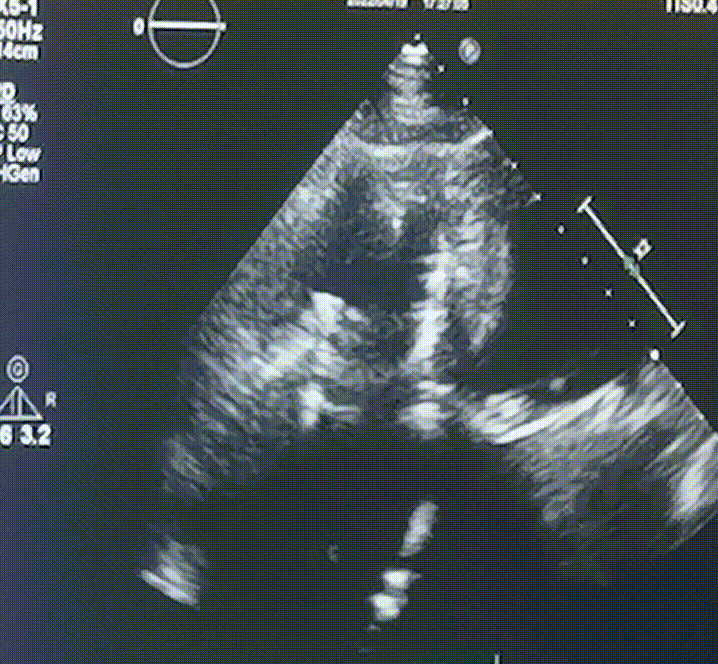

术前超声提示:

1.右心、左房明显增大;

2.二尖瓣人工机械瓣功能正常,无瓣周漏;

3.三尖瓣环巨大扩张,收缩期瓣叶对合不拢,收缩期三尖瓣房侧见大量反流信号,反流面积15-20cm²,TRVmax:240cm/s,跨瓣压差:23 mmHg。